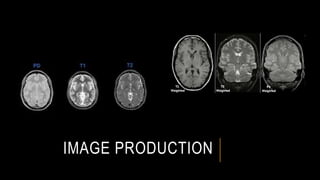

IMAGE PRODUCTION